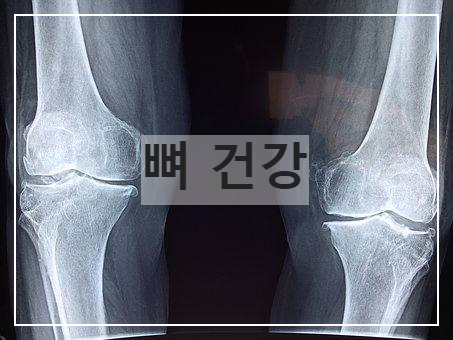

1. 뼈, 골 형성에 도움

혈중 칼슘과 인 수준을 유지하여 뼈, 골 형성에 도움을 줍니다.

칼슘과 인의 소장에서의 흡수율을 향상해 혈중 칼슘 농도와 인의 농도를 유지할 수 있게 합니다.

이는 뼈와 골에 도움이 되는데 성장기에 섭취 시 유리하며 혹은 골밀도 및 골절 예방에 좋아 나이가 많으신 분들에게 좋습니다.